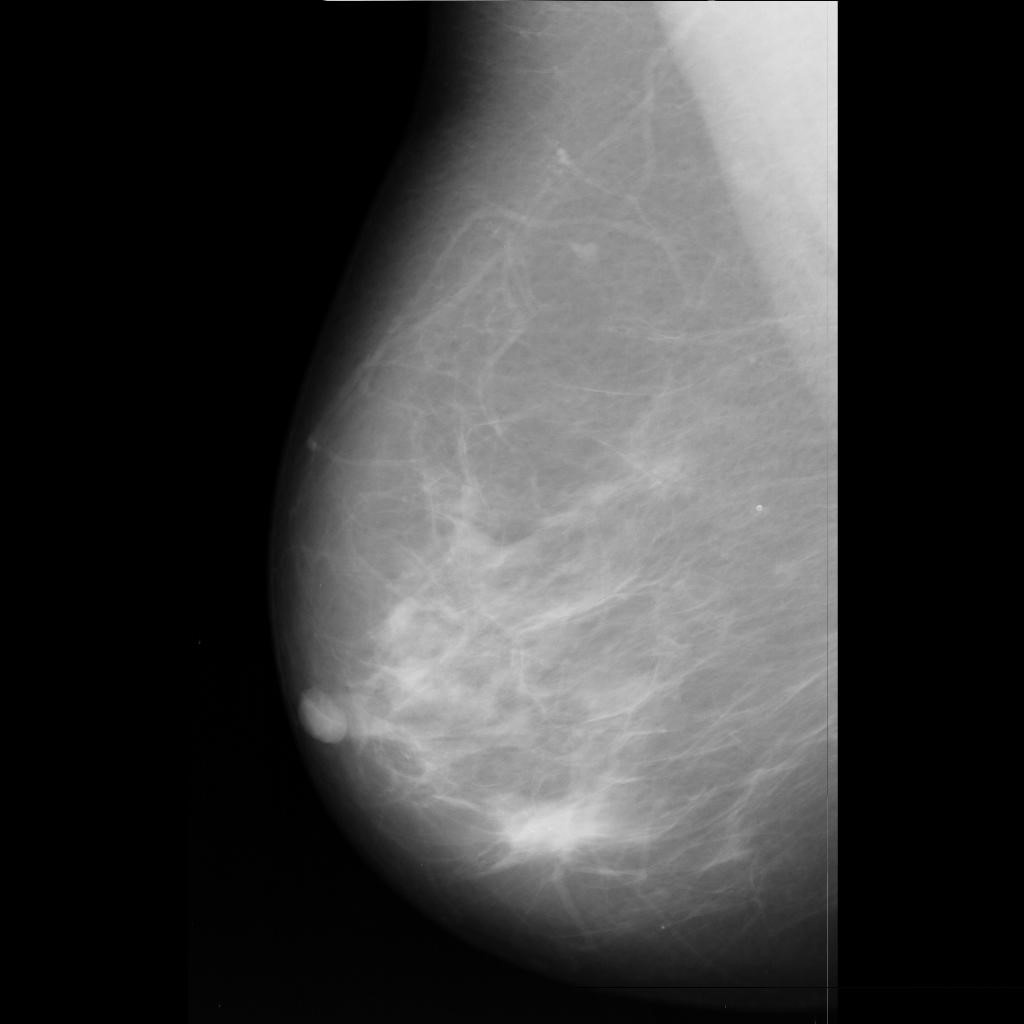

malignant